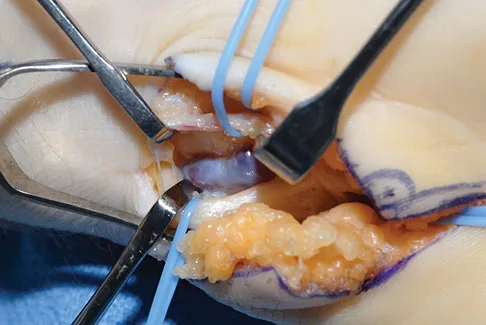

Which of the following is most associated with local recurrence of the lesion seen in the radiograph and MRI scan shown in Figures 27a and 27b?

Correct Answer: Open physes

The lesion is an aneurysmal bone cyst. These lesions are known to have a local recurrence rate of 5% to 50%. Young age, open physes, stage, and type of surgical removal and resulting margin have all been shown to affect the recurrence rate. Chemotherapy is not used in the treatment of aneurysmal bone cysts. Gibbs CP Jr, Hefele MC, Peabody TD, et al: Aneurysmal bone cyst of the extremities: Factors related to local recurrence after curettage with a high-speed burr. J Bone Joint Surg Am 1999;81:1671-1678.